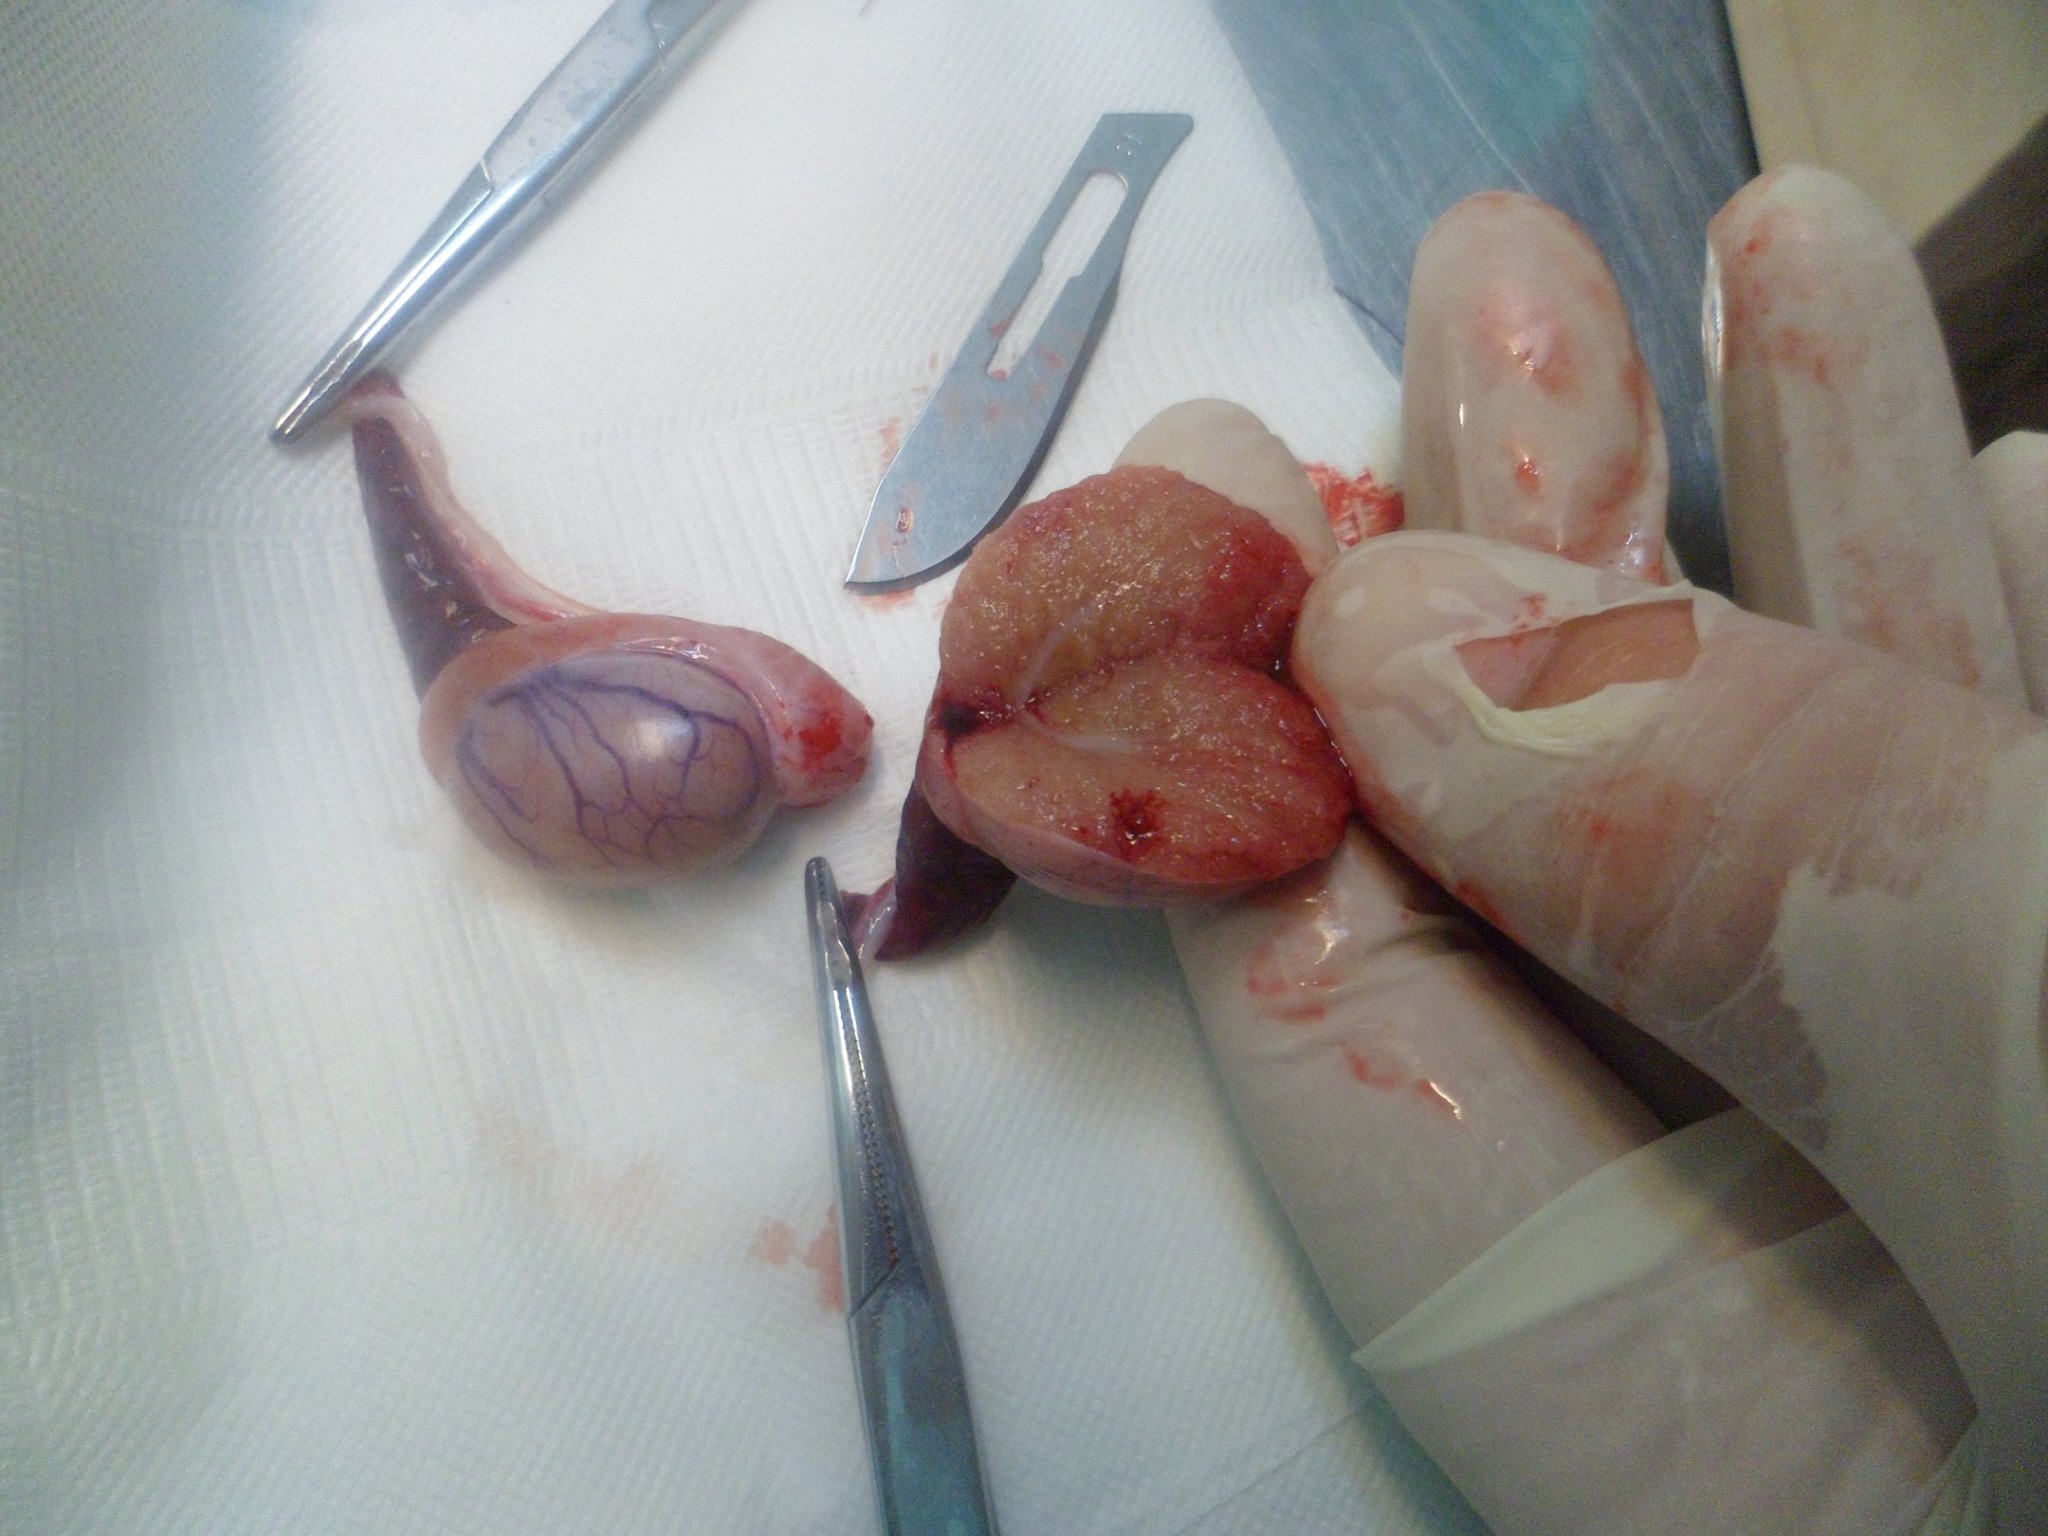

Jete gjati nuk behet jete shkurter (Ndjese per fotot)

Qeni ne foto erdhi ne klinike i mbajtur ne krahe sepse nuk ecte dot vete. I pa fuqishem edhe per te ngrene, shume i dobesuar. Sorrollatur mbi nje muaj e gjysem neper spitale e klinika veterinare i ” diagnostikuar ” prej tyre me semundje nga me te ndryshmet i mjekuar me lloje te ndryshme ilacesh por gjendja vazhdonte te rendohej.

Pas nje kontrolli te kujdesshem dhe analizave te kryera ne klinike nga ana jone u diagnostikua me tumor ne shpretke. U krye nderhyrje kirurgjikale dhe u gjet nje tumor me peshe 1,5 kg.

Pas rehabilitimit post operator ai tashme ka filluar te eci vete, te ushqehet vete dhe te filloje te luaj.

Ju kerkojme ndjese per fotot e tumorit por i botojme per ata profesioniste qe jane vertet te interesuar ne profesionin e tyre.